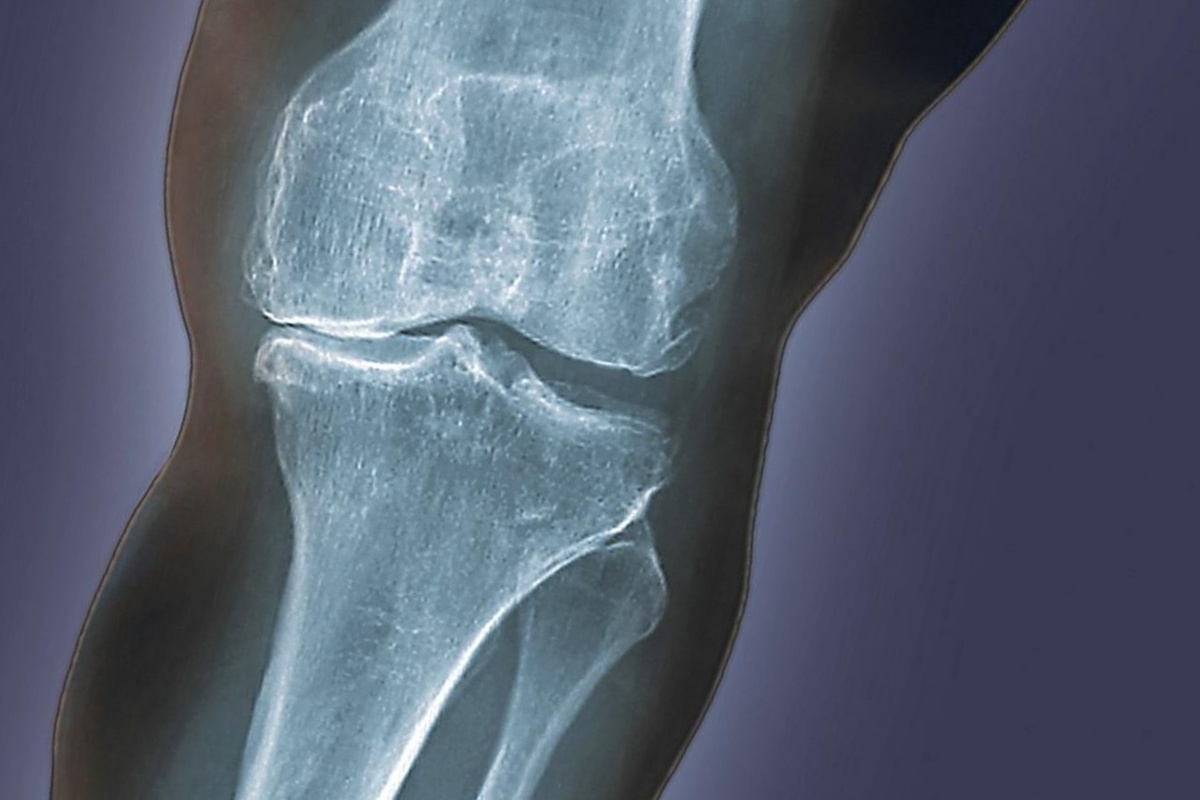

Артроз коленного сустава.